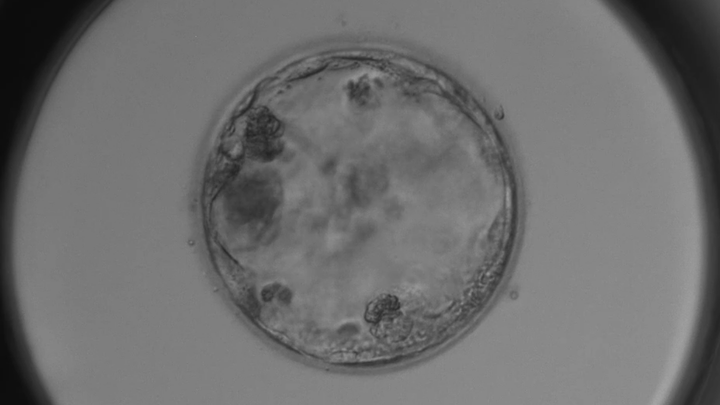

Poor quality embryos

What to do with poor quality embryos?